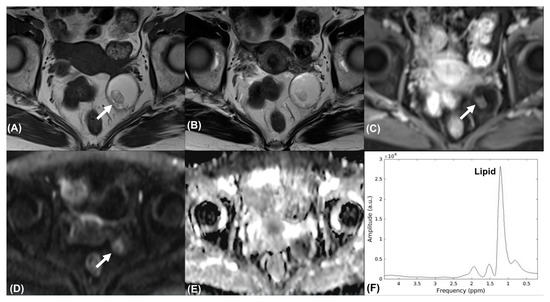

| 17 | Teratoma | No | 3 | FP | TN |

| 18 | Teratoma | No | 2 | FP | TN |